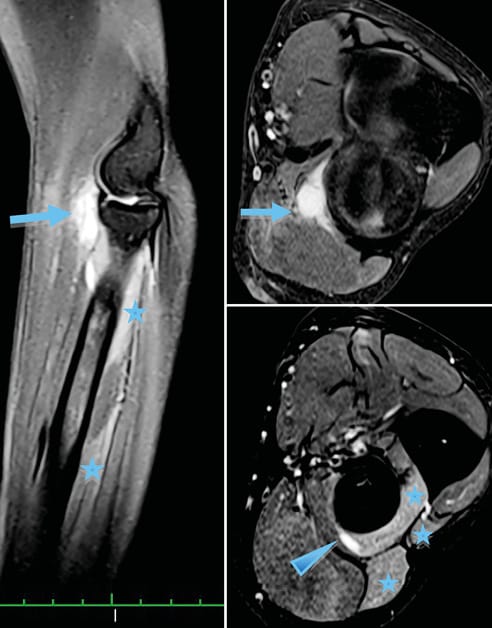

Imagerie Compression de la branche motrice du nerf radial par une récidive postopératoire d'un kyste synovial de l'articulation huméro-radiale